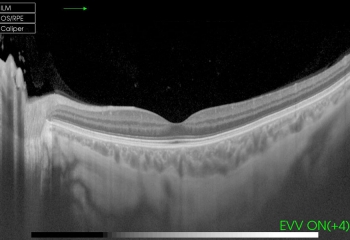

• Liquido o depósitos grasos en la retina y especialmente sobre la macula

• Desprendimiento de retina